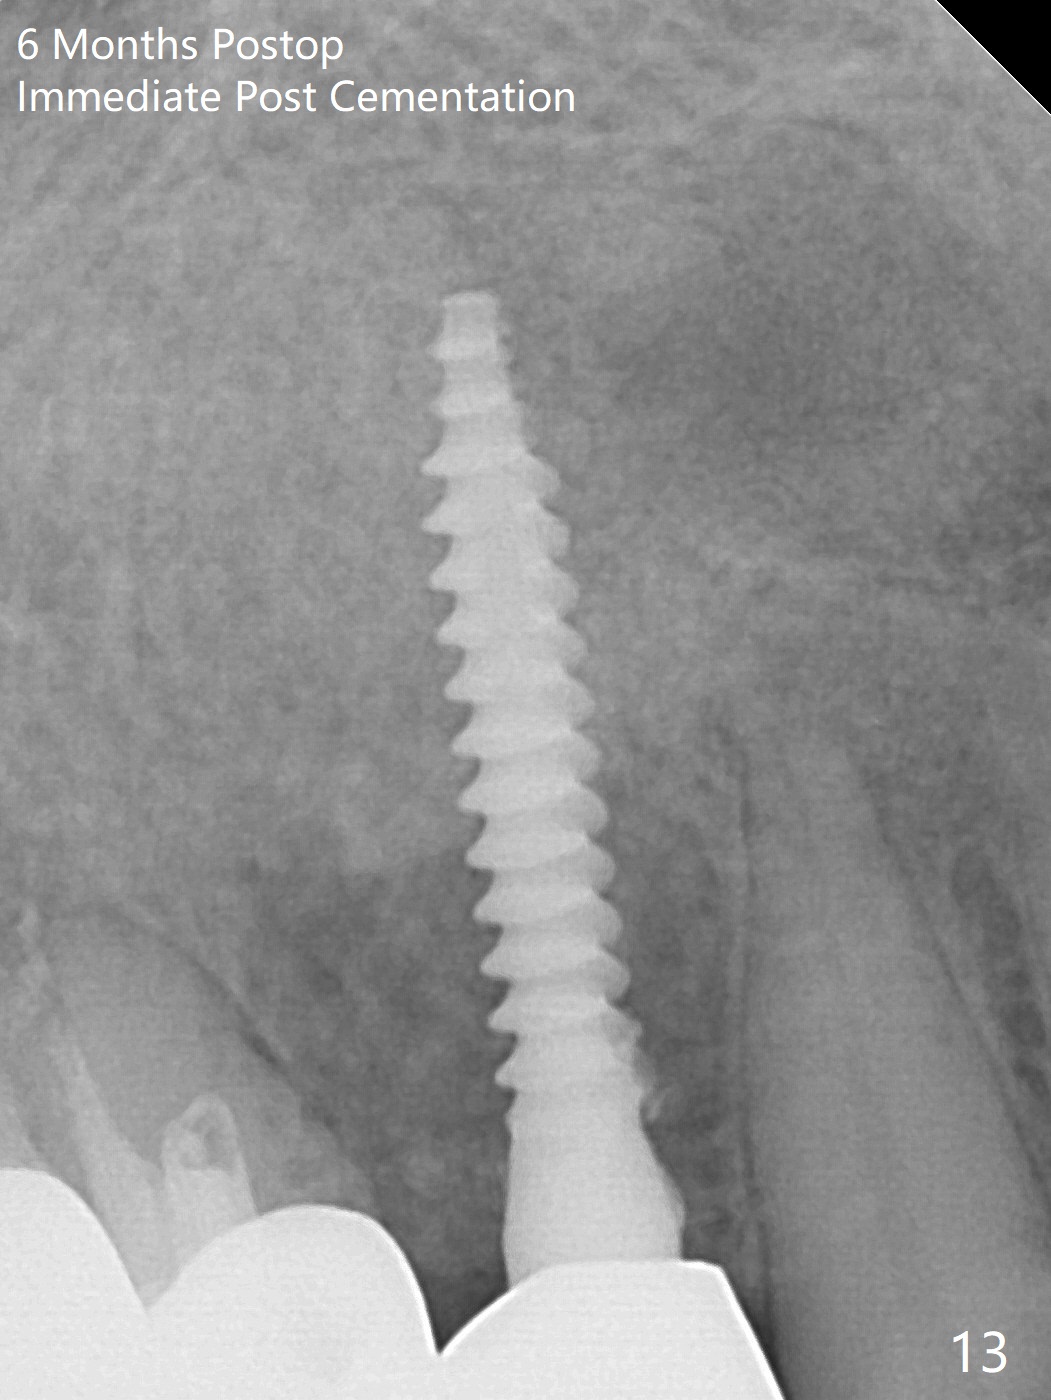

Osteotomy starts with guide and 2.2 mm drill for initial 3.5 mm palatal. A semilunar incision is made buccal to remove the impacted canine (#6 by sectioning). With direct vision buccal and palatal, the final osteotomy is finished free hand with 1.2 and 1.5 mm drills. Initially buccal perforation occurs, the osteotomy route is corrected later (Fig.1). When a 2.5x15 mm 1-piece implant is being placed, it perforates into the buccal concavity again. After redirection, the trajectory seems to be acceptable (Fig.2: CT coronal section). Three coronal implant threads are exposed partially palatal (Fig.3: CT 3-D palatal view). The implant is then turned 2-3 times with insertion torque reaching 40 Ncm. The incision is closed with suture following Osteogen plug placed in the most coronal portion of the socket (Fig.4 P) and allograft (*) in the remaining socket around the apical portion of the implant as well as palatal. The incision does not heal 1 month postop (Fig.5). PRF membrane will be placed next visit. Next visit the wound in fact is healing (Fig.6). PRF is unnecessary. The patient will return for impression 3 months postop. To be cosmetically pleasing, prepare local anesthetic and Laser for gingivectomy (Fig.7 red curved line). There is no bone loss around the implant 3.5 months postop (Fig.8). With topical, minor gingivectomy with laser creates papillae mesial and distal to the implant (Fig.9, 10 (incisal view)). After reline, there is appearance of a canine (Fig.11). The patient returns for impression 5 months postop; there is bone around the apex of the implant (Fig.12 *). The hard and soft tissues remain healthy when final restoration is delivered (Fig.13,14). The buccal plate reforms and #6 socket heals 12 months postop (6 months post cementation, Fig.15). The gingiva remains healthy at #4-6 nearly 2 years post cementation (Fig.16).